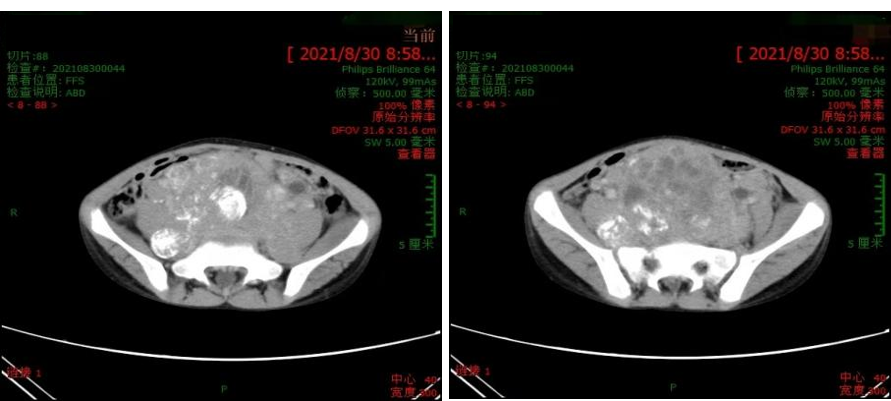

我院CT(2021.08.30):下腹部至盆腔内不规则混杂信号包块(约135.9mm×73.7mm×216.4mm),考虑神经母细胞瘤;骨盆、股骨上段及椎体骨质信号不均匀,不排除骨浸润;双肾输尿管积水。

外院PET/CT(2021.09.07):腹盆腔、腹膜后占位(约10.3cm×9.0cm×19.3cm)伴多发转移(左锁骨上区、腹盆腔、椎间孔及盆壁淋巴结,双侧肩胛骨、多发椎体及部分附件、骨盆及双侧股骨上段)。